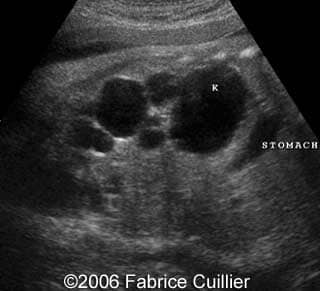

This is a 24- year-old-primigravida scanned at our unit at 21 weeks. During the first trimester, the nuchal translucency and the triple test were normal. At the end of the second trimester, the sonographer diagnosed a left polycystic kidney. The right kidney was normal with a normal corticomedular differentiation. The bladder was also normal. The patient refused additional investigations. We performed a scan at 21 weeks. The ultrasound findings were:

• an abnormal polycystic left kidney (34 X 17 mm) with an abnormal corticomedullar differentiation. This kidney was on the lumbar fossa.

Transverse view of the normal right kidney and the abnormal left kidney